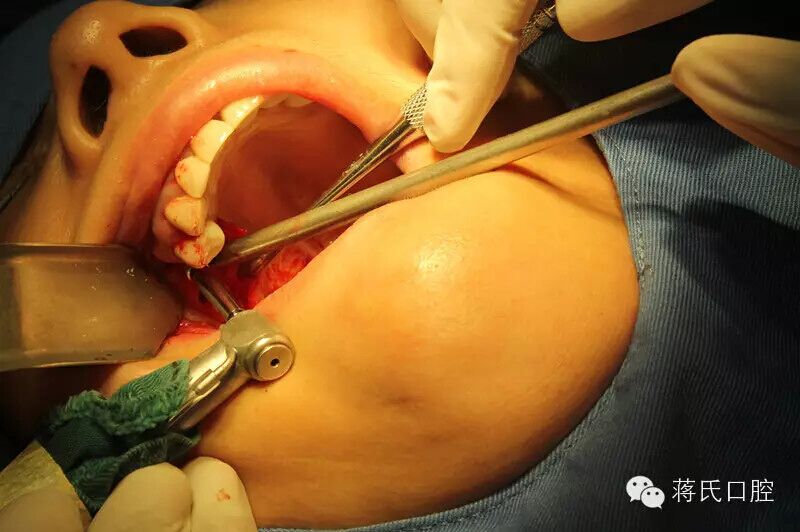

2.右側(cè)種植中

3.備洞過程中收集自體骨

4.右側(cè)備洞后,以骨擠壓內(nèi)提升方式

5.種植體植入過程中